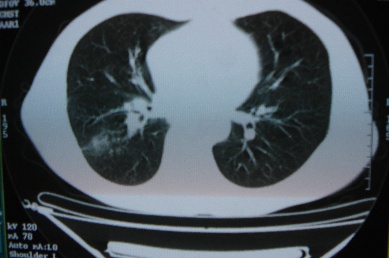

ct10716,男,59岁。发热咳嗽一天,咯血一次入院。

病灶中心有低密度,气体,病灶周围炎性浸润可能为肺脓肿,量体温、查个痰就是了,但肺脓肿一般都多少会有点兄水的。左肺下局部密度减低,小叶中心肺气肿。

病灶边缘较模糊,中心见低密度影及少量气影,宽基与胸膜相连,周围见炎性浸润,考虑右下肺脓肿。

病灶边缘较模糊,中心见低密度影及少量气影,宽基与胸膜相连,周围见炎性浸润,考虑右下肺脓肿。建议治疗后复查。

右下肺病灶,边缘模糊,中心见低密度坏死区及气体影,结合病史较短,以发热为主,考虑右下肺脓肿,建议抗炎治疗后复查。